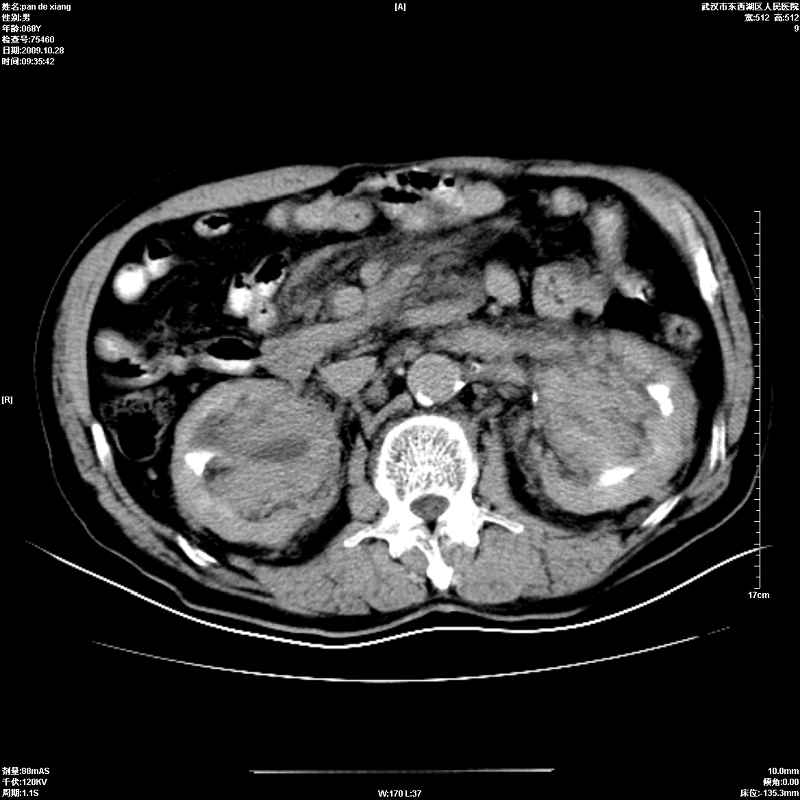

以下是引用杀毒软件在2009-10-28 20:41:00的发言:[br]结合临床考虑---白血病双肾改变或淋巴瘤。

以下是引用zxl51642在2009-10-29 9:59:00的发言:[br]结合临床“单克隆免疫球蛋白血症”,考虑双肾为继发损害并肾功能不全(尿中大量igg及少量iga、igm等大分子免疫球蛋白滤出所致继发损害),椎前软组织肿块为髓外造血。与浆细胞瘤有区别,平扫时有战友说的很清楚。